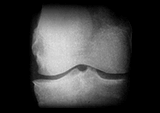

まず問診や触診を行った上で、関節のすき間や変形などの状態を調べるレントゲン(X線)検査が行われます。このとき診断によく使われるのが、変形性ひざ関節症の重症度を示すグレードという指標。グレードは1から4までに分けられており、2以降が変形性ひざ関節症と診断される基準です。グレード2が初期、3が進行期、4が末期と対応しており、進行に伴って関節の隙間が狭くなったり、骨が大きくとがる骨棘(こつきょく)ができたりします。

Kellgren-Lawrence分類(K-L分類)

ひざ関節の隙間が狭くなり始める、変形性ひざ関節症の初期段階。骨の大きな変形はないが、わずかに骨棘の形成が確認できる。